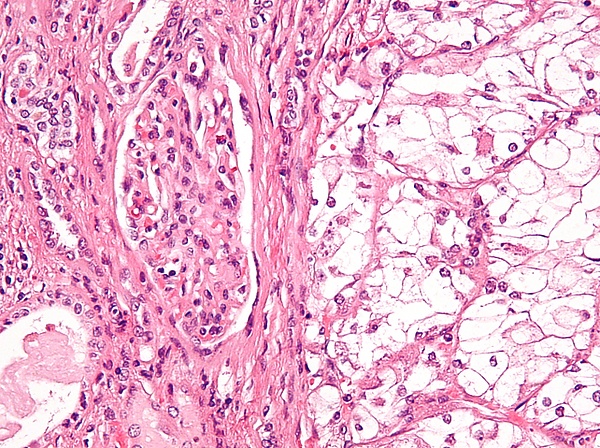

| Микрофотография, демонстрирующая наиболее частый тип рака почки — светлоклеточный (окраска гематоксилином и эозином) | |

Ранее рак почки классифицировали по типу клеток и характеру роста. Позже было установлено что рак почки в абсолютном большинстве — смешанный. Современная классификация основывается на морфологических, цитогенетических и молекулярных исследованиях, а также иммуногистохимическом анализе и выделяет 5 видов почечно-клеточного рака[34]:

- светлоклеточный рак почки

В рамках упоминавшегося выше многоцентрового кооперированного исследования 2012 года гистологический тип опухоли почки после операции был описан у 7357 из 7813 больных раком почки, присутствовавших в базе данных. При этом светлоклеточный вариант рака был выявлен у 6774 (92,1 %) пациентов, папиллярный — у 303 (4,1 %), хромофобный — у 175 (2,4 %), рак собирательных трубочек — у 17 (0,2 %), а наличие саркомоподобного рака в опухоли отмечалось у 88 пациентов. Частота выявления светлоклеточных и несветлоклеточных форм почечно-клеточного рака заметно отличалась от данных, полученных в начале 2000-х гг. в зарубежной клинической практике (где на долю светлоклеточного варианта приходилось 80—90 % злокачественных опухолей, папиллярного — 10—15 %, хромофобного — 4—5 %, рака из собирательных трубочек — менее 1 %, а 7 % случаев осталось неклассифицированными[16]); это, возможно, связано с определённой недооценкой частоты хромофобного и особенно папиллярного вариантов, допускаемой российскими морфологами[33].